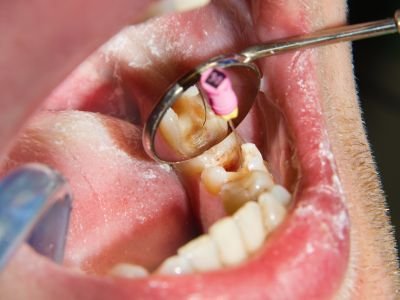

Así tendrá un presupuesto y un tiempo estimado para la realización del mismo.

🫵🏼Reservamos la agenda con los especialista que requieras